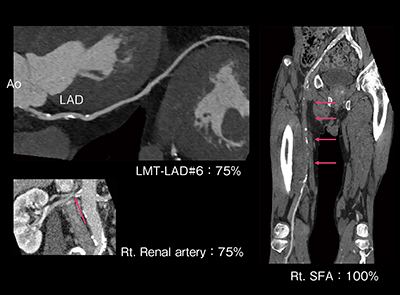

症例は75歳,男性。2012年から右目が全体的に霞む症状が出現し,2013年3月に当院脳神経外科を紹介受診した。右内頸動脈狭窄を認め,内頸動脈ステント留置術の適応であった。糖尿病の加療中であり,心電図変化を認めたため,無症状ではあるが動脈硬化スクリーニング精査目的にて循環器内科を受診した。ABIは右が0.89で異常値,左も境界値であった。そこで一括撮影を行ったところ,左前下行枝(LAD)の狭窄,浅大腿動脈(SFA)の完全閉塞,右腎動脈起始部に75%狭窄が認められた(図5)。さらに,冠血流予備量比を測定したところLADは0.71,右腎動脈は0.70であり,超音波検査でも腎動脈の高速血流が認められた。

このため,本症例はまず頸動脈の治療を行い,続いてLMからLADの経皮的冠動脈形成術と,腎動脈およびSFAの末梢血管インターベンションが施行された。

図5 症例:冠動脈・腎動脈・下肢動脈CTA一括撮影